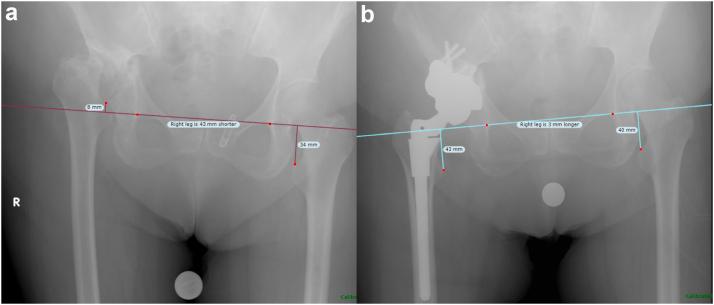

A single-institution retrospective case series of primary THA patients treated with TMA between 2010 and 2019 was performed. Patient demographics, complications, and revisions were recorded. Cup position, center of rotation, leg length, and radiolucent lines were assessed radiographically. The Kaplan-Meier method was used to compute implant survivorship.

Twenty-six patients (30 hips) were included with average age of 52.6 ± 15.3 years (range: 22-78) and mean follow-up of 4.1 ± 2.1 years (range: 2.0-8.9). Most TMAs were indicated for developmental dysplasia of the hip (n = 18; 60.0%). On average, hip center of rotation was lowered 1.5 ± 1.3 cm and lateralized 1.2 ± 1.5 cm, while leg length and global offset were increased by 2.4 ± 1.2 cm and 0.4 ± 1.0 cm, respectively. At final follow-up, 3 hips (10.0%) required revision: one (3.3%) for aseptic loosening and 2 (6.7%) for instability. No patients had progressive radiolucent lines at final follow-up. Five-year survival with aseptic loosening and all-cause revision as endpoints was 100% (95% confidence interval: 90.0%-100.0%) and 92.1% (95% confidence interval: 81.3%-100.0%), respectively. One patient required revision for aseptic loosening after the 5-year mark.

对2010年至2019年间接受TMA治疗的初次THA患者进行单机构回顾性病例系列研究。记录患者人口统计学资料、并发症和翻修情况。通过影像学评估髋臼杯位置、旋转中心、肢体长度和透亮线。采用Kaplan-Meier方法计算植入物生存率。

纳入26例患者(30髋),平均年龄52.6±15.3岁(范围:22 - 78岁),平均随访4.1±2.1年(范围:2.0 - 8.9年)。大多数TMA用于髋关节发育不良(n = 18;60.0%)。平均而言,髋关节旋转中心降低1.5±1.3 cm,向外移位1.2±1.5 cm,而肢体长度和整体偏移分别增加2.4±1.2 cm和0.4±1.0 cm。在末次随访时,3髋(10.0%)需要翻修:1髋(3.3%)因无菌性松动,2髋(6.7%)因不稳定。在末次随访时,没有患者出现进展性透亮线。以无菌性松动和全因翻修为终点的5年生存率分别为100%(95%置信区间:90.0% - 100.0%)和92.1%(95%置信区间:81.3% - 100.0%)。1例患者在5年标记之后因无菌性松动需要翻修。